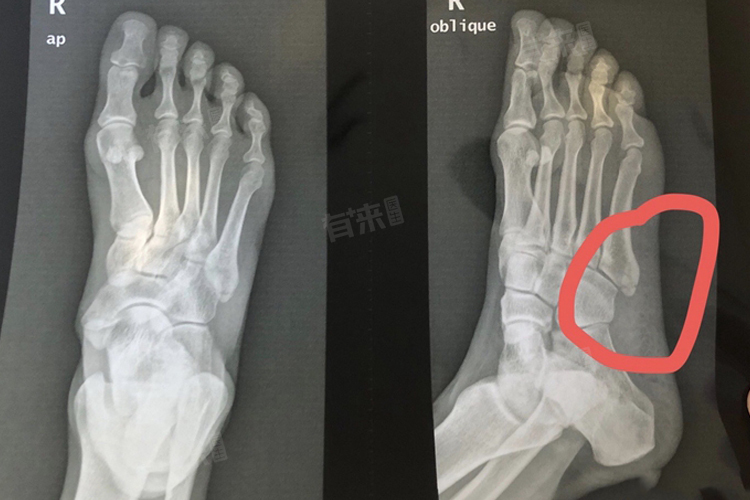

患者在康复期间应定期前往医院复查,通过X光片检查骨折的愈合情况,并根据医生的建议调整康复计划。在骨折未完全愈合前,患者应避免过早负重行走,以免导致骨折移位或延迟愈合。